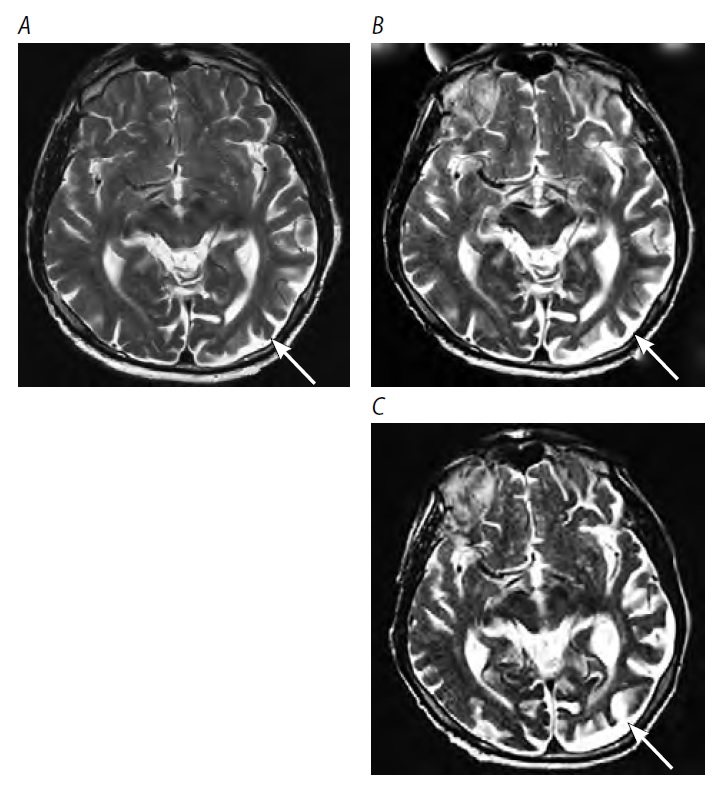

Характерным нейровизуализационным признаком являются атрофические изменения в области сильвиевой борозды доминантного полушария на корональном (или фронтальном) срезе в Т1-ВИ, при этом на других последовательных срезах выявление асимметричной атрофии вызывает затруднения даже у врачей-рентгенологов (рис. 2).

Рис. 2. МРТ головного мозга пациента с аППА. Стрелки — атрофия левой задней лобно-островковой области. / Fig. 2. Brain MRI of a patient with aPPA. Arrows indicate atrophy of the left posterior fronto-insular region.